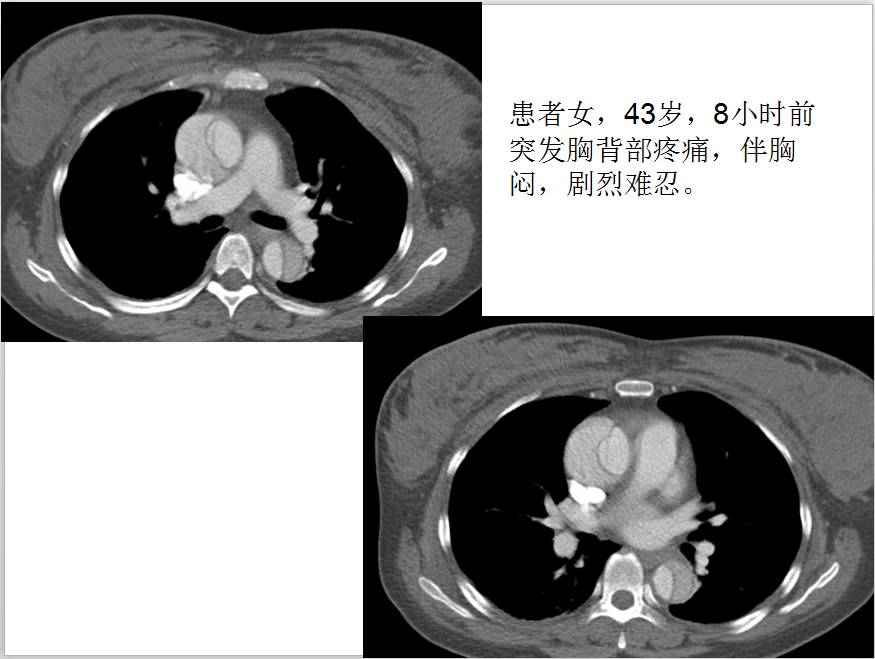

【病例学习】妊娠合并主动脉夹层一例CT影像学表现

CT表现:自主动脉根部起至腹主动脉肾动脉水平可见撕裂之动脉内膜瓣影,子宫腔内可见胎儿影。

诊断结果:妊娠合并主动脉夹层(I型)。